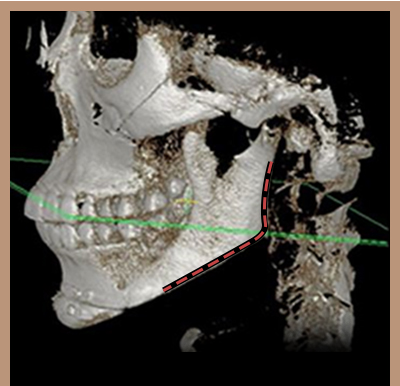

如果耳下方頜角切除過度,會變成不自然的“刀削臉”。

這是為什麼呢?因為耳下方頜角切除越多,會讓臉型越尖的錯誤想法所致。耳下方頜角與正面線條沒有直接關係。

耳下方頜角與耳垂距離維持在1.5cm左右,才更自然。另外,過度切除耳下方頜角容易產生二次角,這是因為截骨線的坡度不夠緩和。

WIAD長曲線方下巴縮小術在耳下保留1.5cm的自然距離,使下頜緣曲線柔美。

如果耳下方頜角切除過度,會變成不自然的“刀削臉”。 這是為什麼呢? 因為耳下方頜角切除越多,會讓臉型越尖的錯誤想法所致。 耳下方頜角與正面線條沒有直接關係。耳下方頜角與耳垂距離維持在1.5cm左右,才更自然。 另外,過度切除耳下方頜角容易產生二次角,這是因為截骨線的坡度不夠緩和。 WIAD長曲線方下巴縮小術在耳下保留1.5cm的自然距離,使下頜緣曲線柔美。